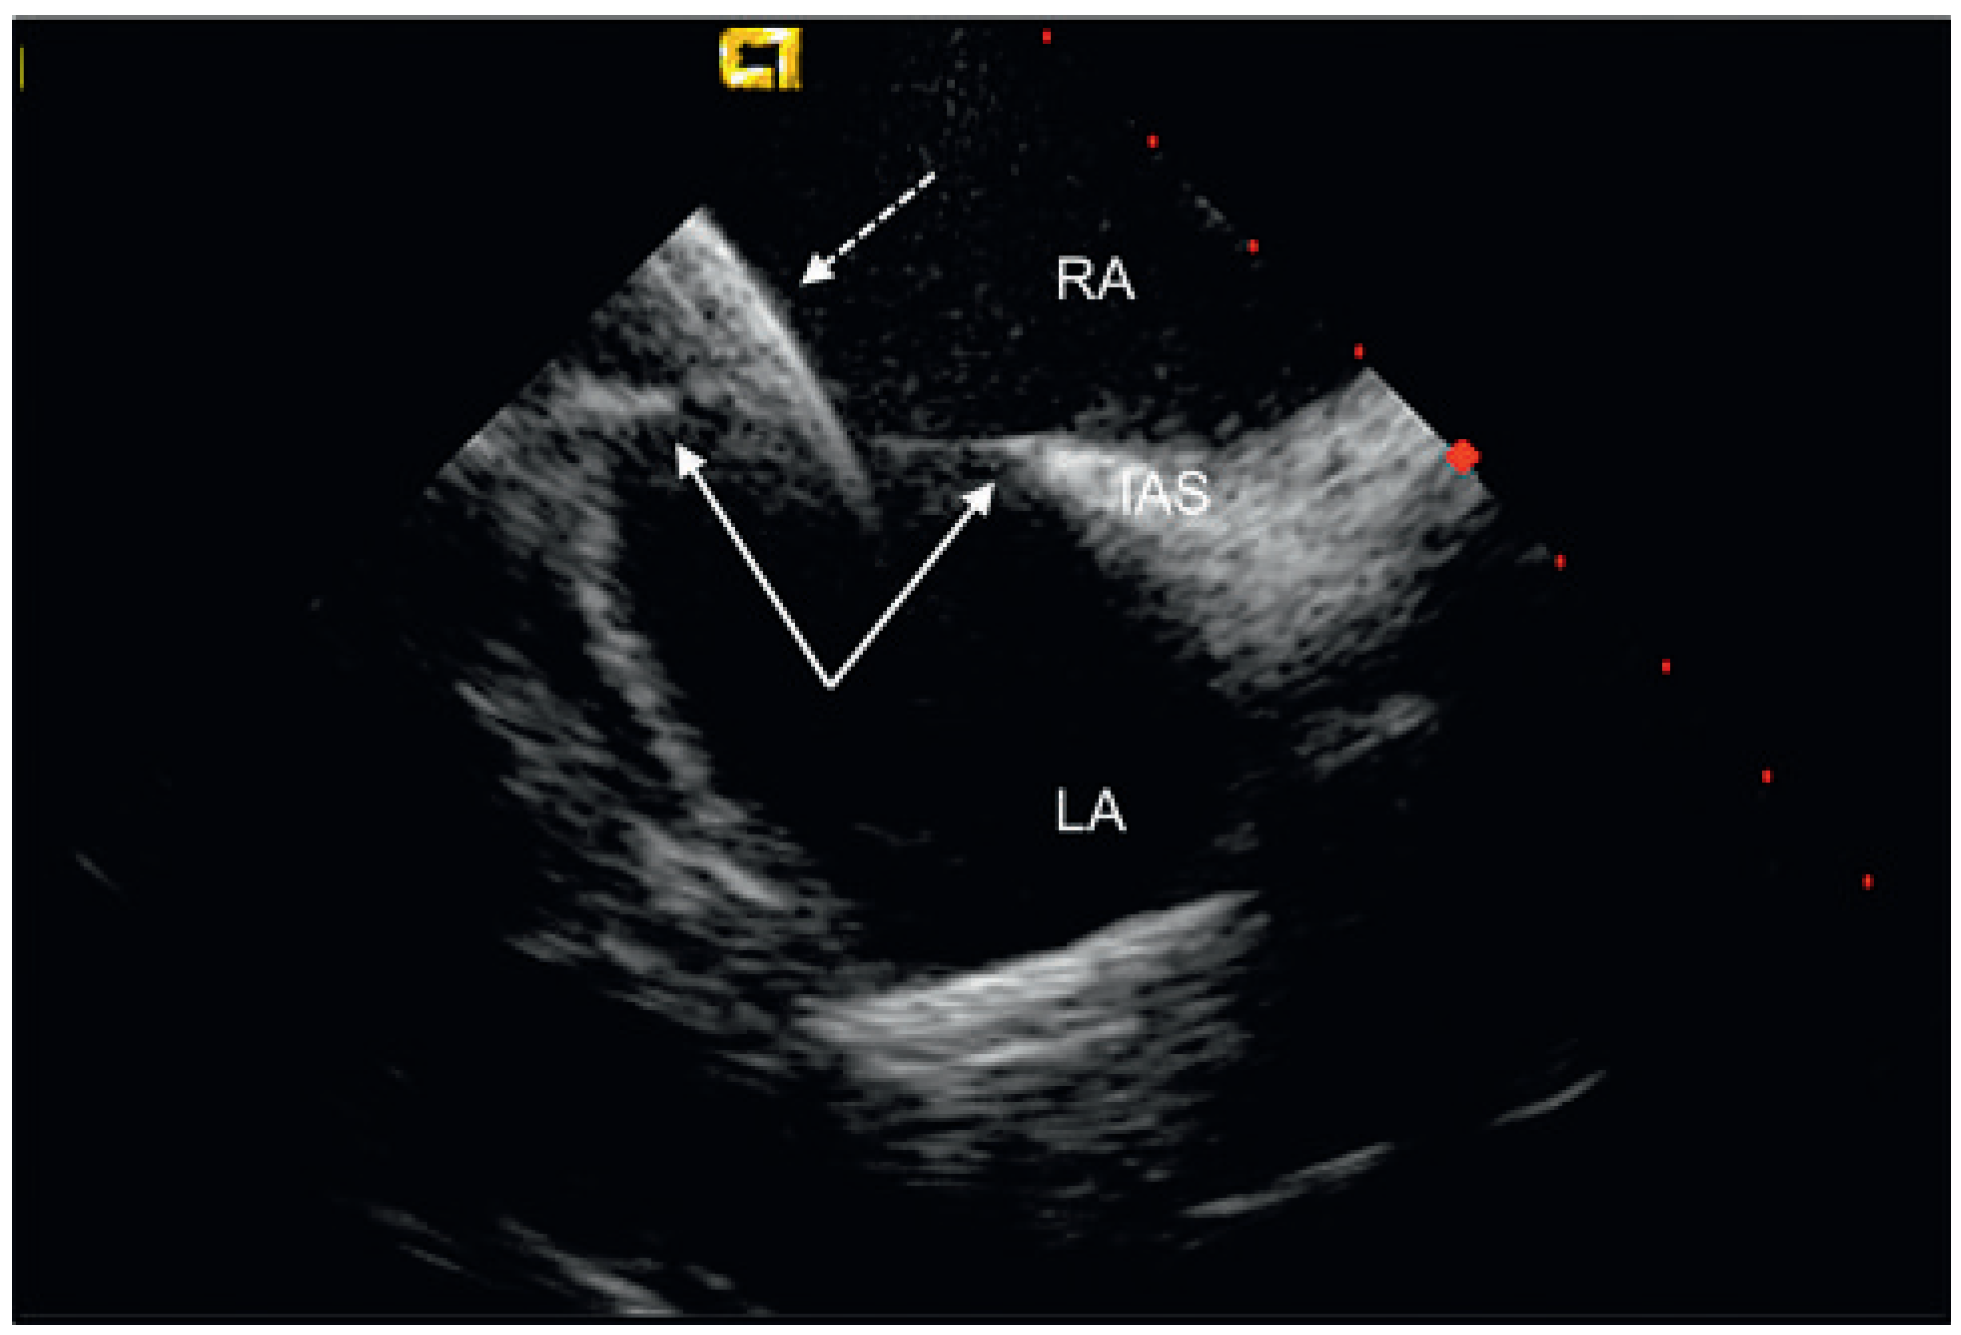

Percutaneous Implantation of an ASD Occluder with Intracardiac Ultrasound